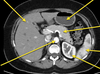

label this CT